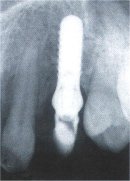

Fall Nr. 2 Nur auf dem Röntgenbild ist etwas zu erkennen, was sich unter diesem Zahn verbirgt: Ein Implantat. Fall Nr. 2